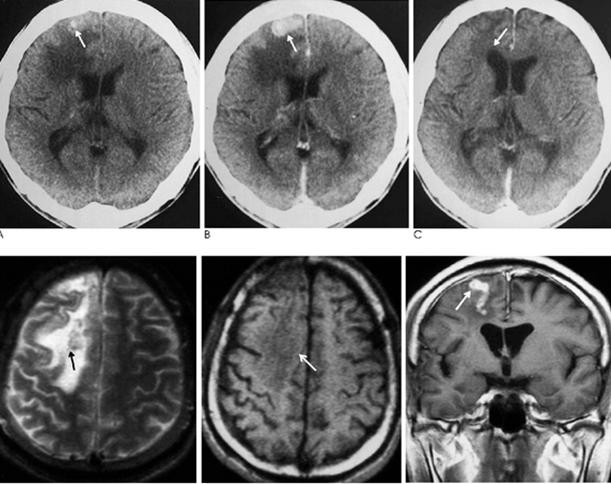

Hình 10-11. Một số thương tổn do sán nhái Spirometra spp. trên cơ quan thần kinh

Hình 12. Ấu trùng sán nhái gây thương tổn nhiều vị trí khác nhau trên nhu mô não

Xác định vị trí thương tổn bằng chụp cắt lớp vi tính (CT) hoặc chụp cộng hưởng từ (MRI) sẽ giúp cho chẩn đoán bệnh sán nhái tốt, nhất là thể sán não. Rạch và loại bỏ thương tổn và xác định loài sán để đưa ra chẩn đoán xác định. Trong trường hợp thể não, xét nghiệm ELISA dịch não tủy hoặc xét nghiệm huyết thanh sẽ giúp ích nhiều cho chẩn đoán, nhưng thường được khẳng định sau khi đã bắt được con sán. Chụp CT giúp hỗ trợ cho chẩn đoán lâm sàng, thường thương tổn có đặc điểm giảm âm, dãn não thất, các nốt bất thường, có nhiều vùng can xi hóa. Các chuyên gia khuyên nên chụp lại CT để đánh giá sự thay đổi kích thước cũng như vị trí tổn thương để chỉ định điều trị kịp thời nếu vẫn còn thương tổn.

CT và MRI đặc biệt hiệu quả trong chẩn đoán bệnh sán nhái ở não vì các hình ảnh thể hiện trong nhu mô não. Thông qua phân tích hồi cứu 25 ca sán trên não từ năm 2000-2006, tác giả Song và cộng sự tìm thấy một số đặc điểm có thể áp dụng như một khung chẩn đoán áp dụng trong tương lai mà không cần thực hiện sinh thiết hay phẩu tích mô thương tổn. Đặc điểm tìm thấy phổ biến nhất là dấu đường hầm ("tunnel sign") trên phim MRI cho thấy vết di chuyển của sán, trong khi đó hình ảnh thường thấy là hình tăng đavòng tròn hợp nhất, hay nhiều hình tràng hạt (thường là 3-6 vòng). Siêu âm tổng quát với nhiều loại đầu dò khác nhau cũng cho thấy có hữu ích trong chẩn đoán nhiễm trùng sán nhái trên các mô mềm và một số tạng.

Các nghiên cứu của Song còn đề nghị bổ sung với các dữ liệu về bệnh sử lâm sàng, xét nghiệm ELISA và hình ảnh của MRI hay CT scans đủ để chẩn đoán bệnh sán nhái. Tuy nhiên, các thương tổn này đôi khi dễ bị nhầm lẫn với thương tổn do lao. Trong một trường hợp sán nhái ở não không được chẩn đoán trong vòng 4 năm, khi chụp đã cho thấy chùm vòng tròn do chuyển từ bên phải sang bên trái của não, cuối cùng sán đã được tìm thấy qua sinh thiết.